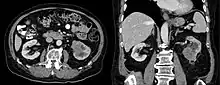

Collecting duct carcinoma

Collecting duct carcinoma (CDC) is a type of kidney cancer that originates in the papillary duct of the kidney. It is rare, accounting for 1-3% of all kidney cancers.[2] It is also recently described; a 2002 review found just 40 case reports worldwide.[3] Previously, due to its location, CDC was commonly diagnosed as renal cell carcinoma or a subtype of renal cell carcinoma.[4] However, CDC does not respond well to chemotherapy drugs used for renal cell carcinoma, and progresses and spreads more quickly.